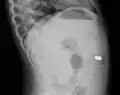

اشعه ایکس یک باتری ۹ میلی متری را در روده نشان میدهد

اشعه ایکس جانبی، یک باتری ۹ میلی متری را در روده نشان میدهد